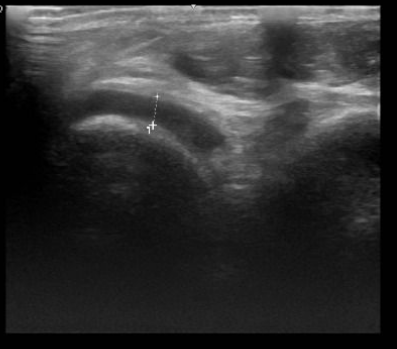

Hình ảnh siêu âm khớp cổ chân trái cúa anh H cho thấy có tràn dịch khớp (ảnh BSCC).

Từ triệu chứng lâm sàng, bệnh nhân được chẩn đoán sơ bộ: theo dõi gút cấp/béo phì độ II và được chỉ định thực hiện xét nghiệm máu, chẩn đoán hình ảnh chuyên sâu. Kết quả xét nghiệm cho thấy anh H có chỉ số acid uric máu tăng cao; rối loạn chuyển hóa lipid máu (tăng cholesterol và triglycerid); siêu âm khớp cổ chân trái có tràn dịch khớp; siêu âm ổ bụng cho thấy gan nhiễm mỡ độ II; có polyp túi mật.